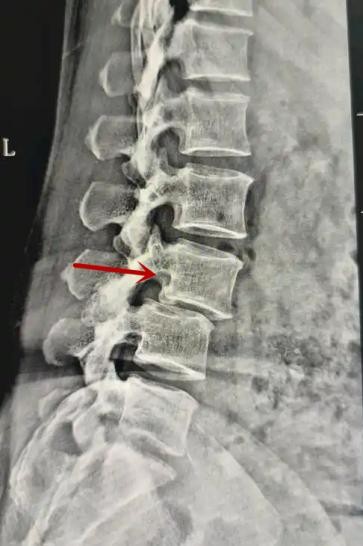

腰椎X線片作為最基礎的影像檢查手段,利于X線穿透人體組織后成像,以其快捷、直觀、價格低廉的特點,X線檢查主要包括腰椎正側(cè)位、雙斜位以及過伸過屈位。主要用于觀察腰椎骨骼的情況,如椎體是否有骨折、骨質(zhì)增生程度、生理曲度的變化、椎體移位的情況等。然而,X線檢查也有它的局限性,無法判斷是骨折的新舊,對于椎體內(nèi)部結(jié)構和周圍肌肉韌帶組織(如脊髓神經(jīng)、椎間盤、韌帶等)的顯示不佳,另外X線作為有輻射檢查,孕婦及嬰幼兒謹慎選擇。

箭頭提示腰1椎骨折

箭頭提示腰3椎體滑脫